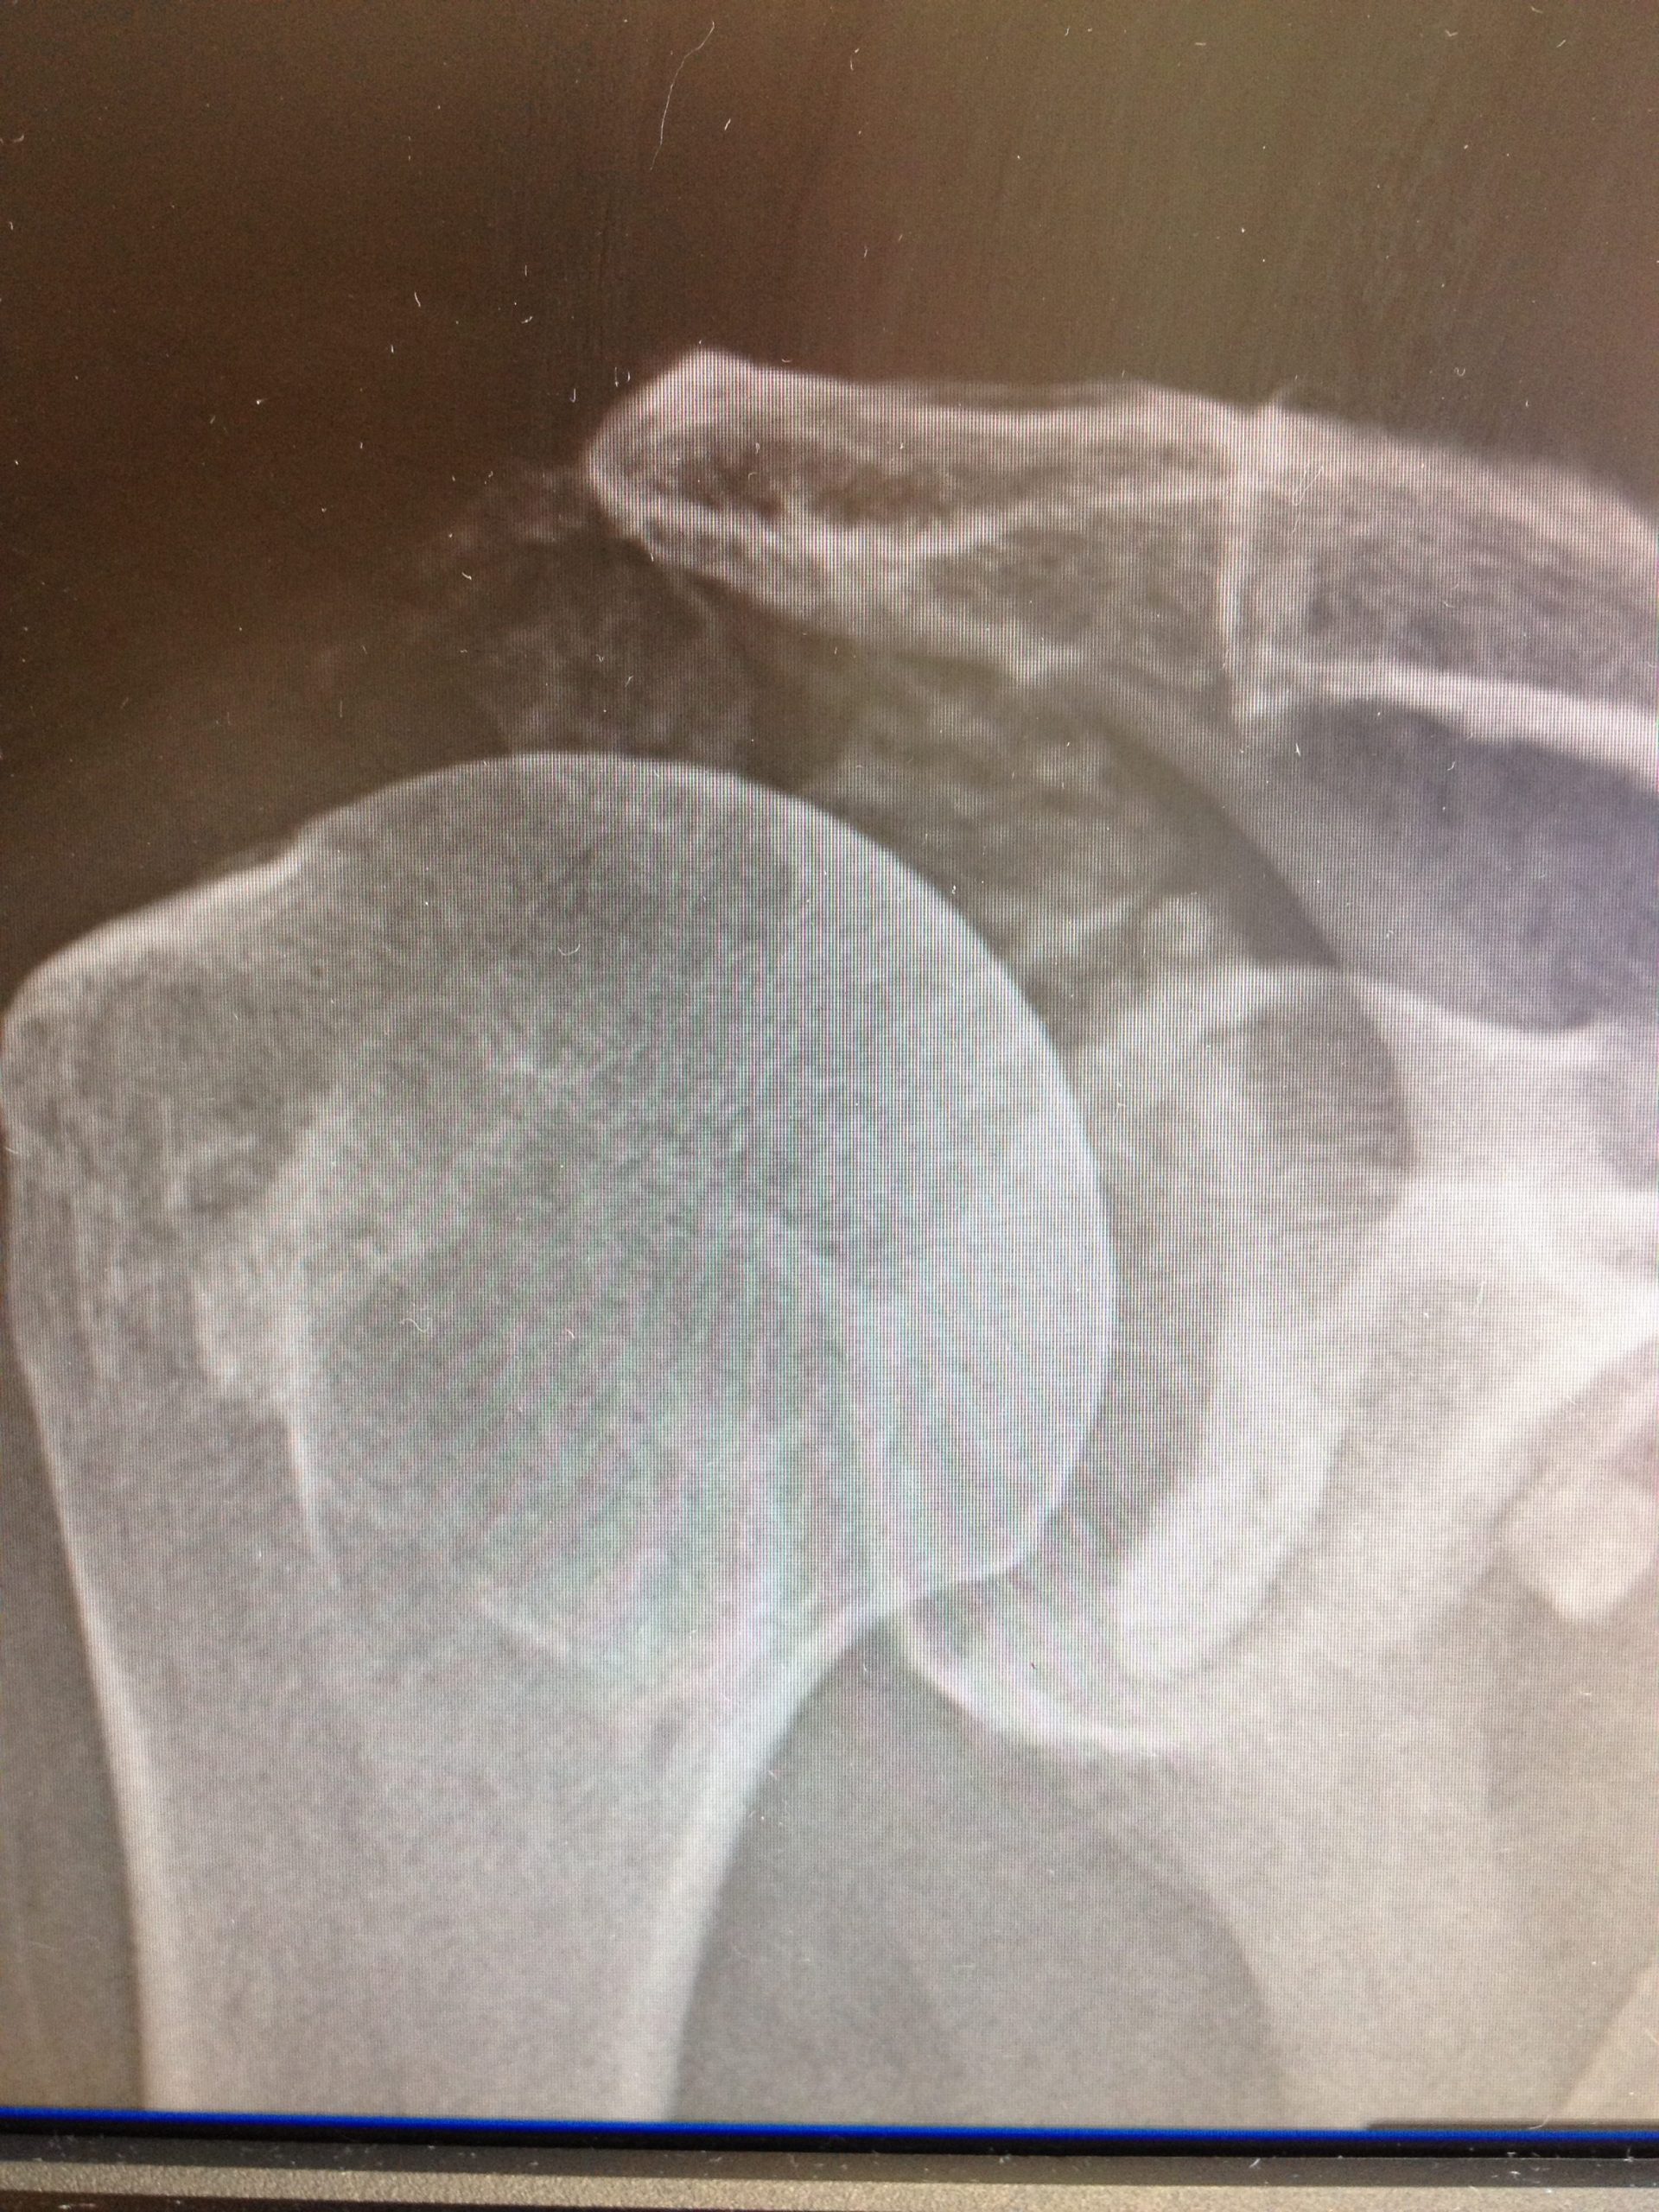

Frozen shoulder can develop spontaneously or from minor injury. There is also a risk of developing this condition following any sort of surgery to the shoulder. Frozen shoulder is a self-resolving condition and will go through three phases as below:>

Phase 1 – the inflammatory phase – this is the worst part of the condition when the shoulder is extremely painful, simple movements or even catching the elbow on a table can be extremely painful. Treatment of this phase is really confined to adequate analgesia and steroid injection for pain relief. This phase can go on for up to six months.

Phase 2 – the frozen phase – as the inflammatory phase resolves the pain should improve to the point where the patient does not require analgesia. At this point the shoulder will still remain quite stiff but there should be a lot less pain. It is at this stage that physiotherapy and possibly surgical intervention may be of benefit.

Phase 3 – the thawing phase – this is where movements will return very slowly and gradually over time. Recovery of all three phases can take anywhere between 12 and 24 months to resolve and generally there is often a loss of 10% global range of movement permanently regardless of whether surgery is performed or not.

Surgery – in order to try and accelerate your recovery, arthroscopic surgery and manipulation of the shoulder may be considered in the frozen phase. This will be carried out as a day case under general anaesthetic and regional anaesthetic to the arm. Three holes are created, the inflammatory tissue is removed and the shoulder gently manipulated. There can be vast improvement in elevation and reaching of the shoulder and on external rotation. Internal rotation (getting the arm around the back to the bra strap for example) is often minimally improved but should improve with time. There is a small risk of fracture with manipulation of any shoulder which is to be expected and the other risks associated with arthroscopy.